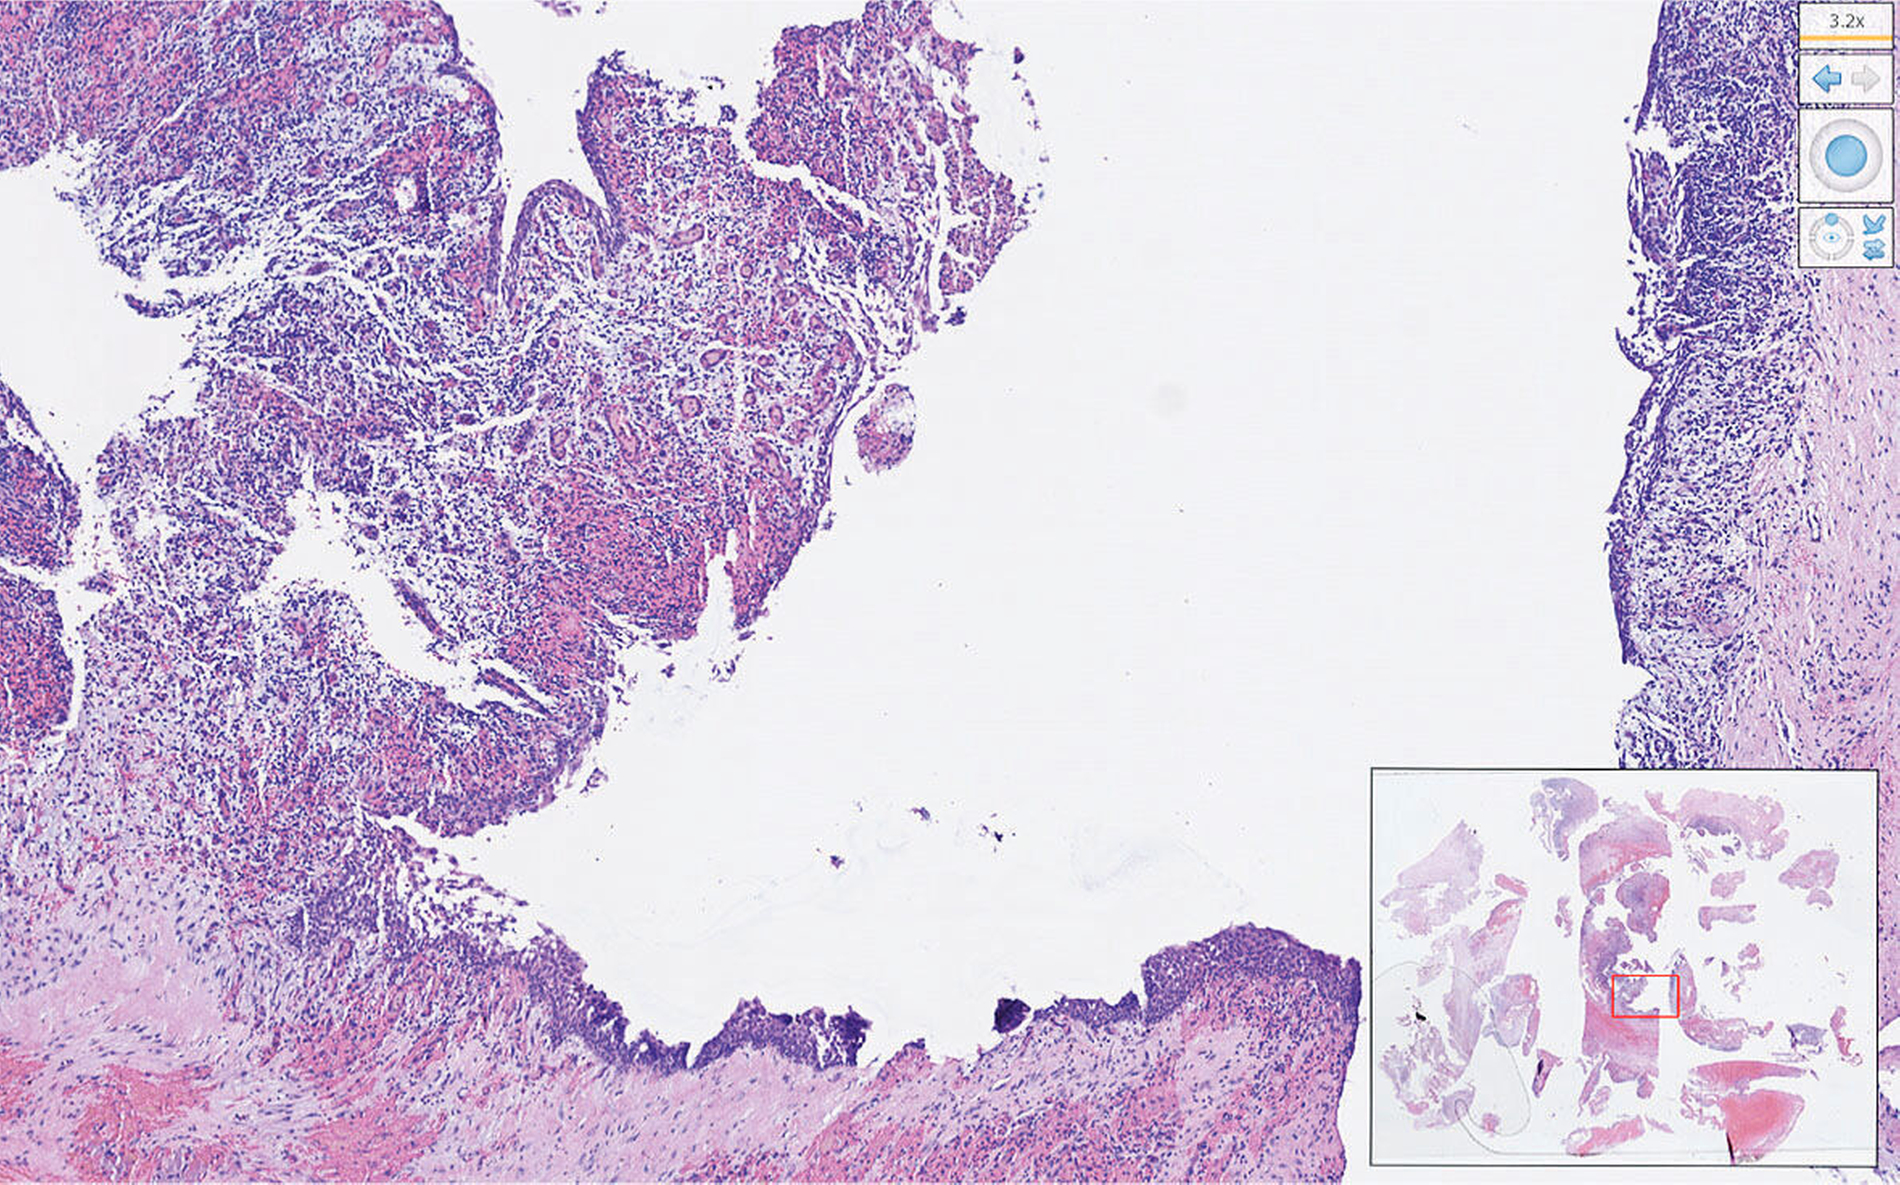

Die histopathologische Untersuchung bestätigte die Verdachtsdiagnose einer nasopalatinalen Zyste (Abbildung 4). Hier zeigte sich eine mit mehrschichtigem Plattenepithel ausgekleidete Zystenwand. Als Ausdruck der florid überlagerten, chronischen Entzündung waren histologisch Einblutungen und gemischtzelliges Entzündungsinfiltrat bestehend aus Lymphozyten, Granulozyten und Plasmazellen erkennbar.

Histologisch zeigt sich eine fibröse Zystenwand, die durch mehrreihiges Flimmer- und Plattenepithel überkleidet ist. In 72 Prozent der Fälle enthalten die Zysten Platten-, Säulen- oder kubisch geformte Epithelanteile; respiratorisches Epithel ist mit einem Vorkommen von 10 Prozent eher selten. Aufgrund der relativen Nähe zur Nasen- und Mundhöhle ist die Art des Epithels relativ variabel. Je nach Lokalisation dominiert Riech- oder Plattenepithel. Die Zystenwand kann Lymphozyten- und Plasmazellen als Ausdruck einer chronischen Inflammation enthalten. Das Vorkommen von neurovaskulären Bündeln, Drüsen und Fettgewebe unterstützt die Verdachtsdiagnose. Aufgrund der möglichen Hyperkeratose können nasopalatinale Zysten histologisch mit der Keratozyste verwechselt werden. Eine maligne Transformation in ein Plattenepithelkarzinom ist prinzipiell möglich, jedoch sehr selten [Shylaja, 2013].